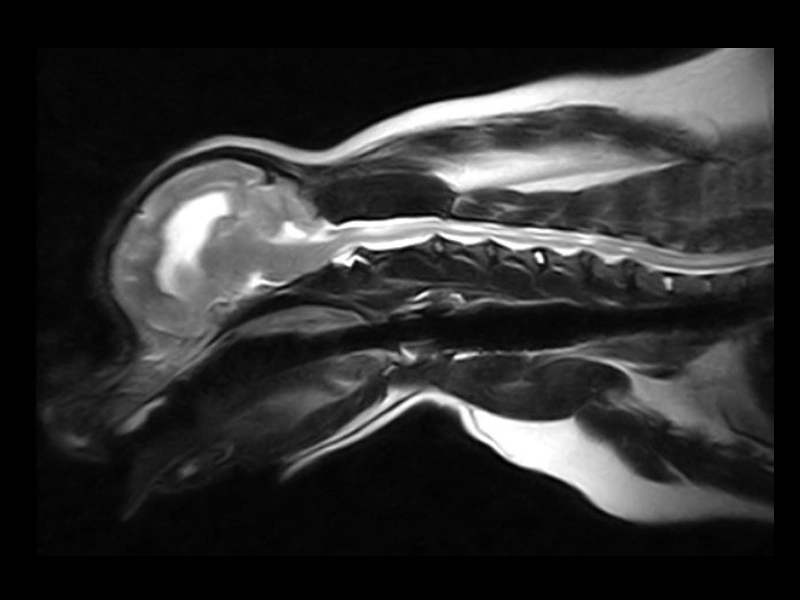

Vet-MR Grande è un sistema RM specializzato, progettato appositamente per la medicina veterinaria. La sua interfaccia utente dedicata semplifica il flusso di lavoro, mentre l’ampia gamma di bobine RF e protocolli anatomici personalizzati garantisce un imaging efficiente e accurato. Lo scanner è predisposto per gestire un'ampia gamma di regioni anatomiche, tra cui neurocranio, colonna vertebrale e piccole articolazioni. Gli utenti esperti hanno la possibilità di personalizzare i parametri di scansione e di memorizzare sequenze personalizzate per usi futuri. Con Vet-MR Grande, i veterinari hanno a disposizione un potente strumento che potenzia le capacità diagnostiche all'insegna dell'efficienza.

Immagini cliniche